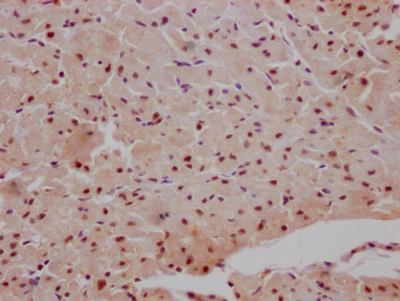

IHC image of CSB-RA990134A0HU diluted at 1:100 and staining in paraffin-embedded human heart tissue performed on a Leica BondTM system. After dewaxing and hydration, antigen retrieval was mediated by high pressure in a citrate buffer (pH 6.0). Section was blocked with 10% normal goat serum 30min at RT. Then primary antibody (1% BSA) was incubated at 4℃ overnight. The primary is detected by a Goat anti-rabbit IgG polymer labeled by HRP and visualized using 0.05% DAB.